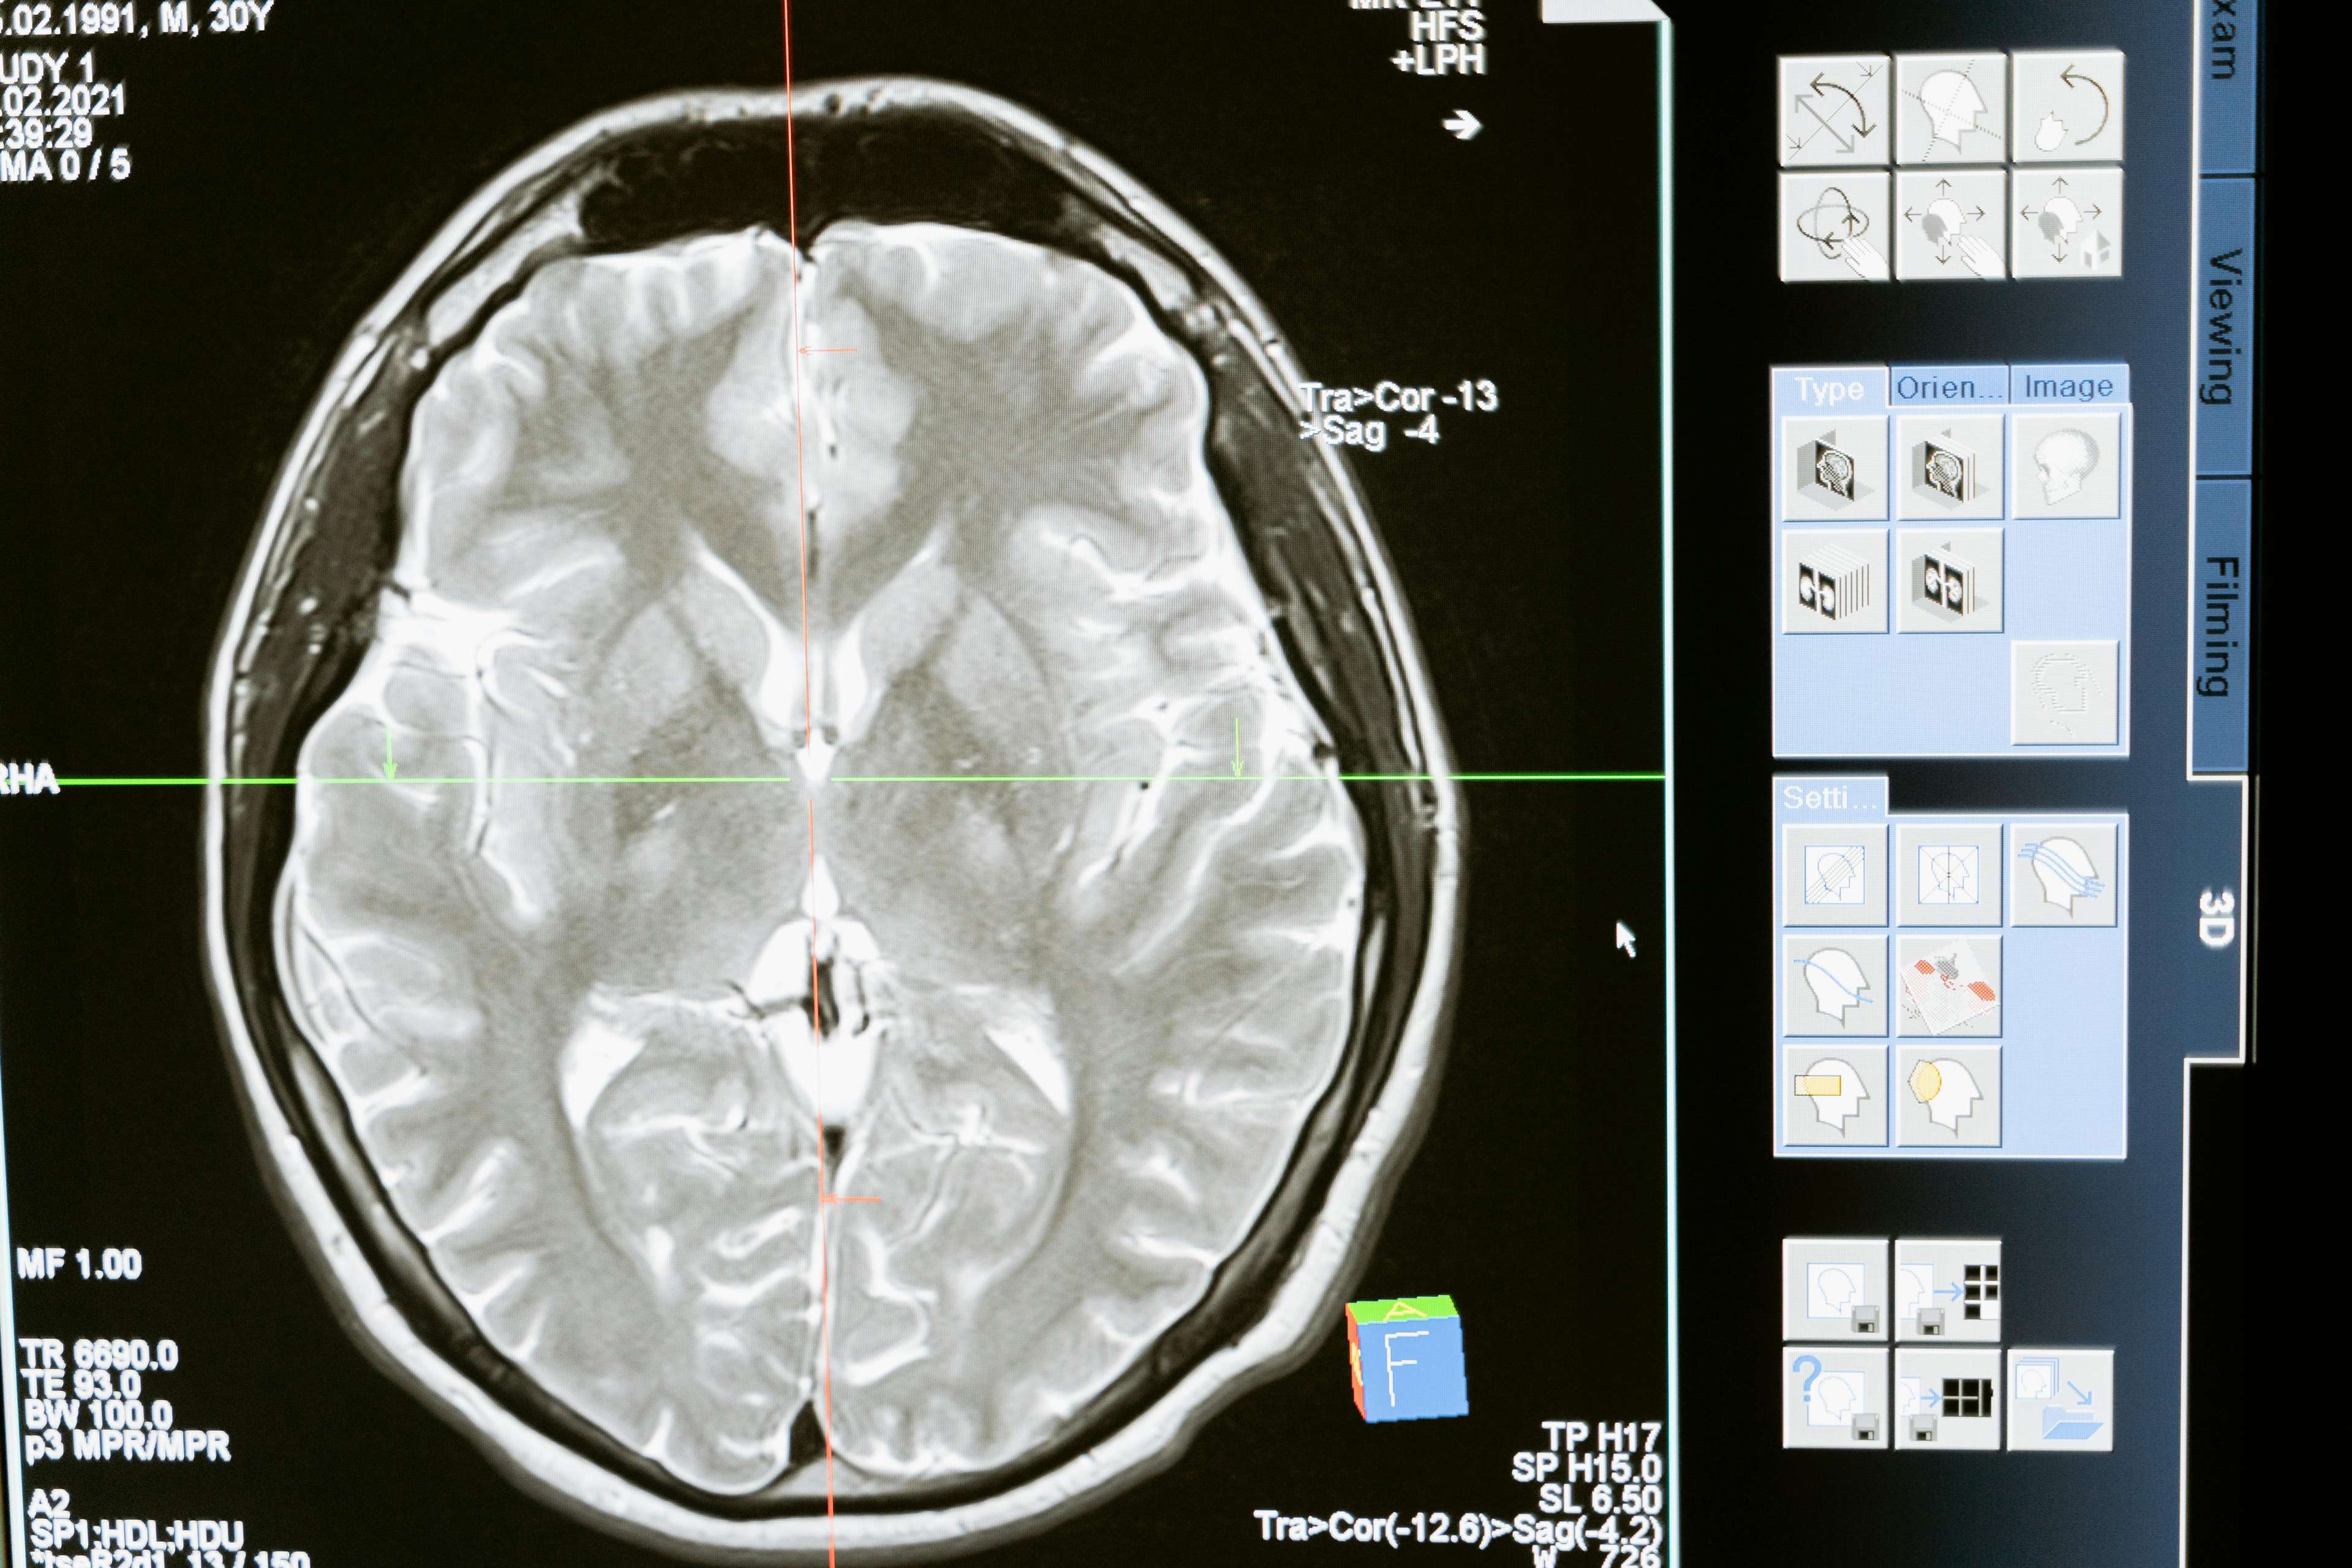

Noong 1990s, isang tagumpay sa teknolohiyang medikal ang nag -alok ng bagong pag -asa para sa mga pasyente ni Parkinson. Ang malalim na pagpapasigla ng utak, isang pamamaraan ng kirurhiko na nagsasangkot ng pagtatanim ng isang aparato na naghahatid ng mga impulses ng elektrikal sa mga tiyak na lugar ng utak, ay ipinakita upang makabuluhang mapabuti ang pag -andar ng motor at mabawasan ang mga sintomas. Sa pamamagitan ng pag -target sa mga lugar ng utak na responsable para sa kontrol ng motor, tumutulong ang DBS upang ayusin ang hindi normal na aktibidad ng utak, na nagpapahintulot sa mga pasyente na mabawi ang kontrol sa kanilang mga paggalaw.